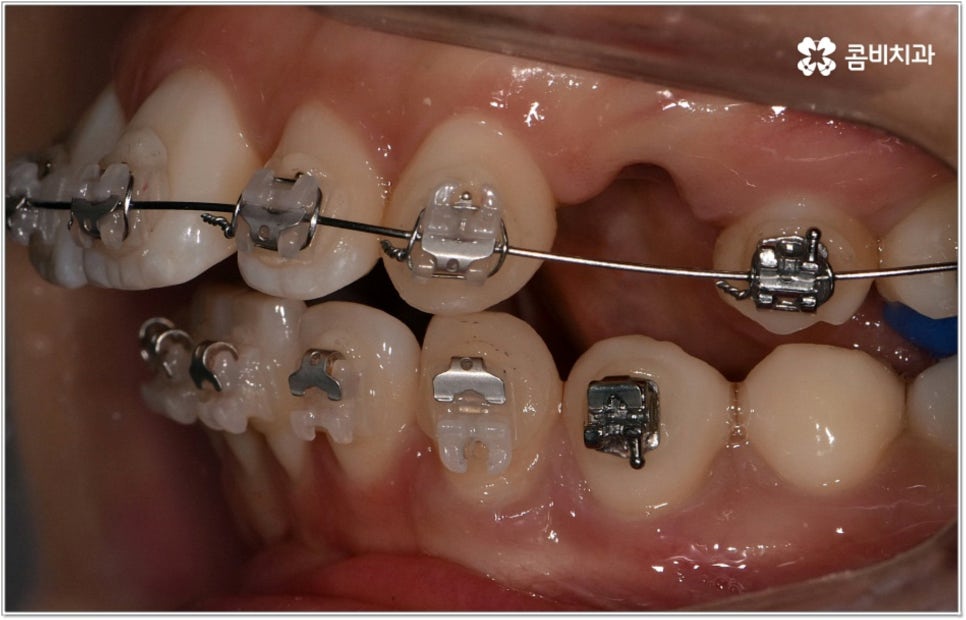

청소년기는 교우 관계에 영향을 많이 받고 외모에 민감할 때라 교정기에 대한 반감이 있을 수 있으나 바로 이때가 치아 이동에 있어 매우 중요한 시기이므로 제대로 이해할 수 있도록 차근차근 설명해 줄 필요가 있는데요. 12~15세 사이, 즉 초등학교 고학년에서 중학교 저학년 사이가 유치에서 영구치로 거의 다 교체되고 잇몸뼈가 계속해서 성장하는 나이이기 때문에 상악과 하악의 균형잡힌 발달을 유도하면서 부정교합을 바로잡고 치열을 가지런하게 만드는데 보다 빠르고 효율적인 만큼 가능하다면 이 시기를 놓치지 않는게 중요한 거예요. 물론 성인분들도 상황에 맞게 교정 치료를 진행할 수 있지만 부정교합의 종류와 정도에 따라 성장기 교정 치료를 진행하는 것이 좀 더 나은 케이스가 있으니 아이의 치열에 관심을 가지고 정확하게 알아보시는 것이 도움이 될 수 있습니다.

무리하지 않고 돌출입치아교정 과정을 진행하기 위해서는 먼저 꼼꼼한 검진 및 분석에 따른 철저한 맞춤 치료 계획 수립이 중요하다고 할 수 있는데요. 특히 3D CT 및 모르페우스 시스템을 통해 현재 아이의 치열이나 연조직, 상하악 관계 등을 자세히 살펴보고 안모 분석 후 교정 치료가 끝난 예상 모습을 시뮬레이션해서 보여주면 환아의 흥미를 유발하고 앞으로 진행될 사항에 대한 이해도를 높여줄 수 있어 긍정적인 영향을 줄 수 있으니 정밀 검진 장비를 갖추고 숙련된 의료진이 치료하는 치과에서 돌출입치아교정 과정을 진행하시길 권유드리고 있어요.

성장기 교정의 경우 턱성장 추이에 맞추어 섬세하게 치아 이동 속도를 결정해야 하므로 구강 검진 외에도 성장판 검진 등을 통해 아이의 전반적인 발달 상황에 대한 유기적인 이해를 바탕으로 치료를 하는 경험 많은 담당의 선생님께 시술을 맡기실 필요가 있습니다. 또한 이렇게 뛰어난 노하우와 기술력을 갖춘 것 뿐 아니라 사전 상담, 전 교정 과정 그리고 사후 관리에 이르기까지 지속적인 소통을 통해 불편한 점이 없는지 세심하게 살피고 개개인의 상황 및 구강 건강을 전체적으로 신경써서 케어해 주는 의료진과 함께 한다면 환아 뿐 아니라 부모님의 입장에서도 더욱 안심이 되고 좋을 거예요.